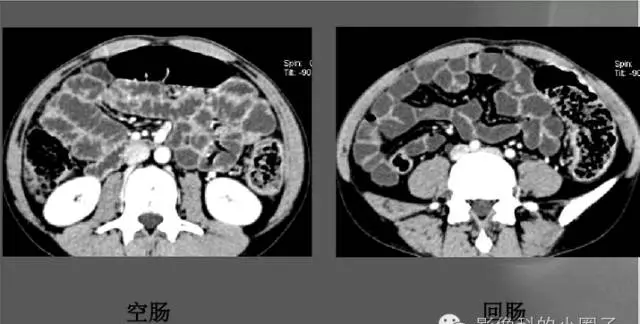

空肠

位于左中上腹、粘膜呈羽毛状、蠕动活跃,大多呈粘膜像。

回肠

位于右中下腹和盆腔。蠕动较弱,大多呈充盈像,表现为短管状,轮廓光滑,加压时可见纵行和斜行粘膜。